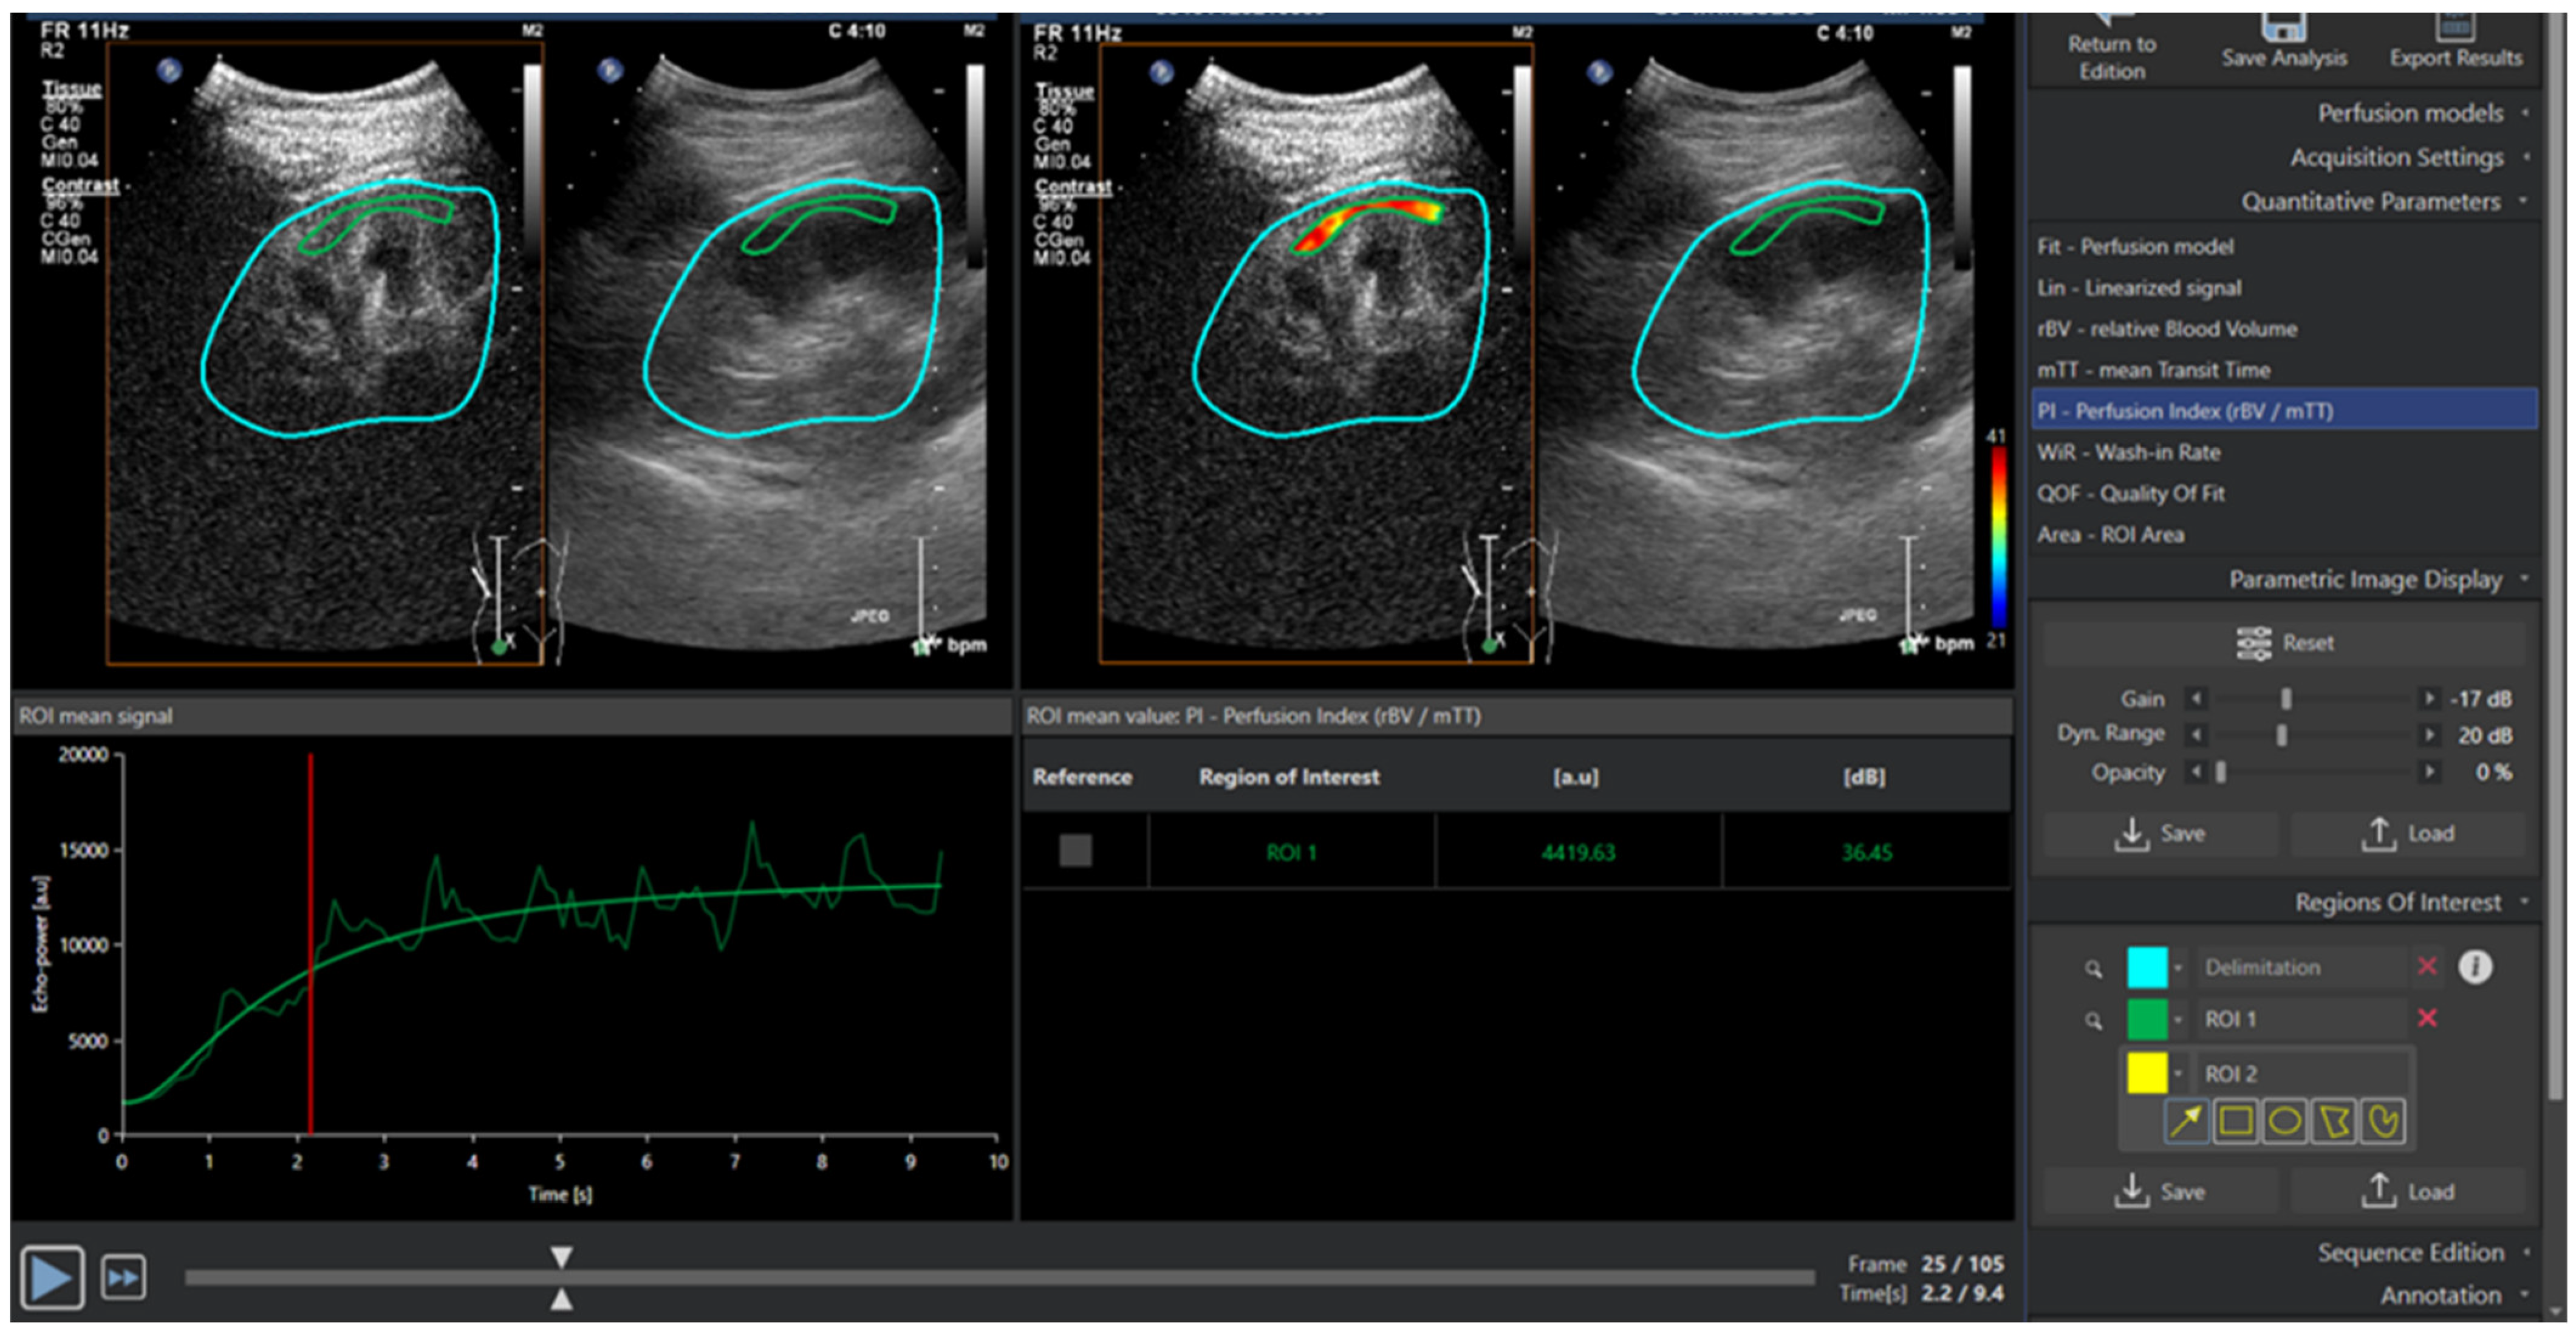

2.3. Renal CEUS Technique

2.5. Image Acquisition

2.6. Image Analysis